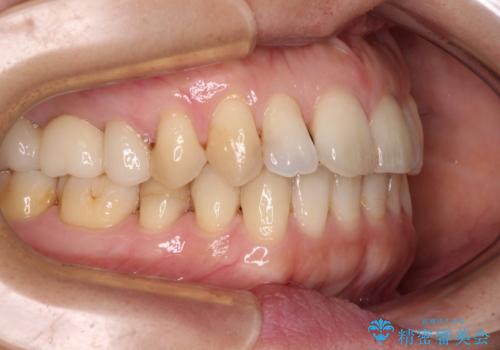

- 上下奥歯の欠損を気にして来院された患者様です。

以前矯正した後戻りにより前歯に叢生が認められたため、矯正治療の提案をしたところ、補綴治療と合わせて矯正治療を行うこととしました。

下顎欠損部はインプラントにて、上顎中間欠損部はブリッジによる補綴治療を行い、他にも気になっている銀歯をセラミックインレーやゴールドインレーにて修復治療を行うこととしました。

後戻りの程度は軽度であったため、インビザライン・ライトを用いて歯列を整えました。

再度後戻りするリスクを最小限に食い止めるため、下顎前歯の舌側を細いワイヤーで固定しました。